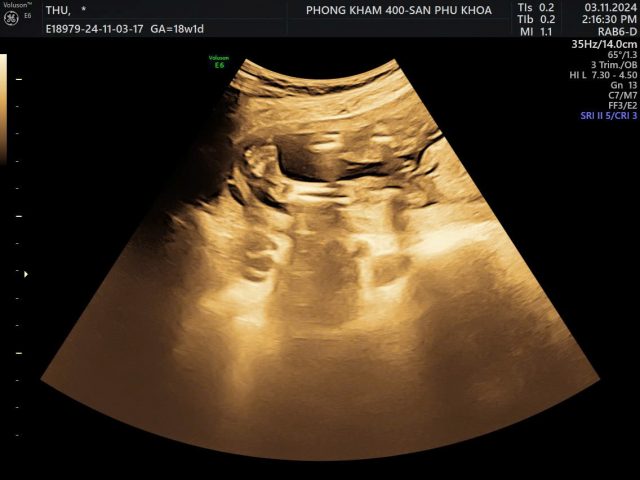

Phụ nữ mang thai nên khám thai định kỳ để sớm phát hiện dị tật ở thai nhi. Trong đó, siêu âm có thể hỗ trợ phát hiện nhiều dị tật hệ xương như bàn chân khoèo, co cứng đa khớp, thiểu sản xương đùi, tật thừa ngón… Nếu trẻ được chẩn đoán hoặc nghi ngờ mắc dị tật bẩm sinh cần có biện pháp can thiệp sớm, tránh ảnh hưởng tới khả năng vận động sau này.